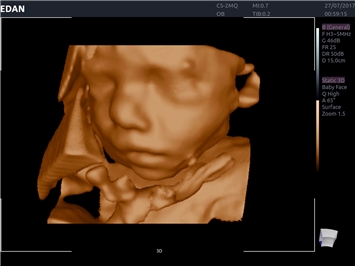

EDAN Acclarix LX4 представляет собой инновационную ультразвуковую систему, построенную на усовершенствованной платформе Acclarix. Сочетание высокого качества визуализации с интеллектуальным рабочим процессом делает эту систему оптимальным выбором для клиник, ценящих эффективность и экономичность.

• 3D/4D-визуализация с автоматическим редактированием объема (eFace)

• Акушерства и гинекологии